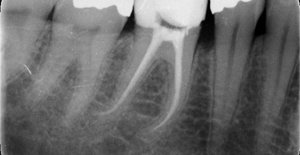

Detersione, sagomatura

e chiusura tridimensionale del canale.

È quella branca dellʼodontoiatria che studia le comunemente dette devitalizzazioni: questo è il punto di partenza principale della maggior parte dei piani di trattamento protesici sui denti naturali ed è quindi estremamente importante una corretta esecuzione nei tempi e nelle tecniche per la durata a lungo termine del trattamento protesico finale.

Anche in questo settore la tecnologia dà una mano con nuove strumentazioni, quali i rivelatori apicali e le strumentazioni meccaniche (non più solo manuali) per ottenere i tre punti fondamentali per il successo: detersione, sagomatura e chiusura tridimensionale del canale.